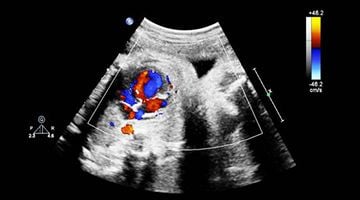

We connect a broad community of sonographers and clinicians who utilise cardiac ultrasound in the echo lab, the intensive care, the operating room, the emergency room and point-of-care.